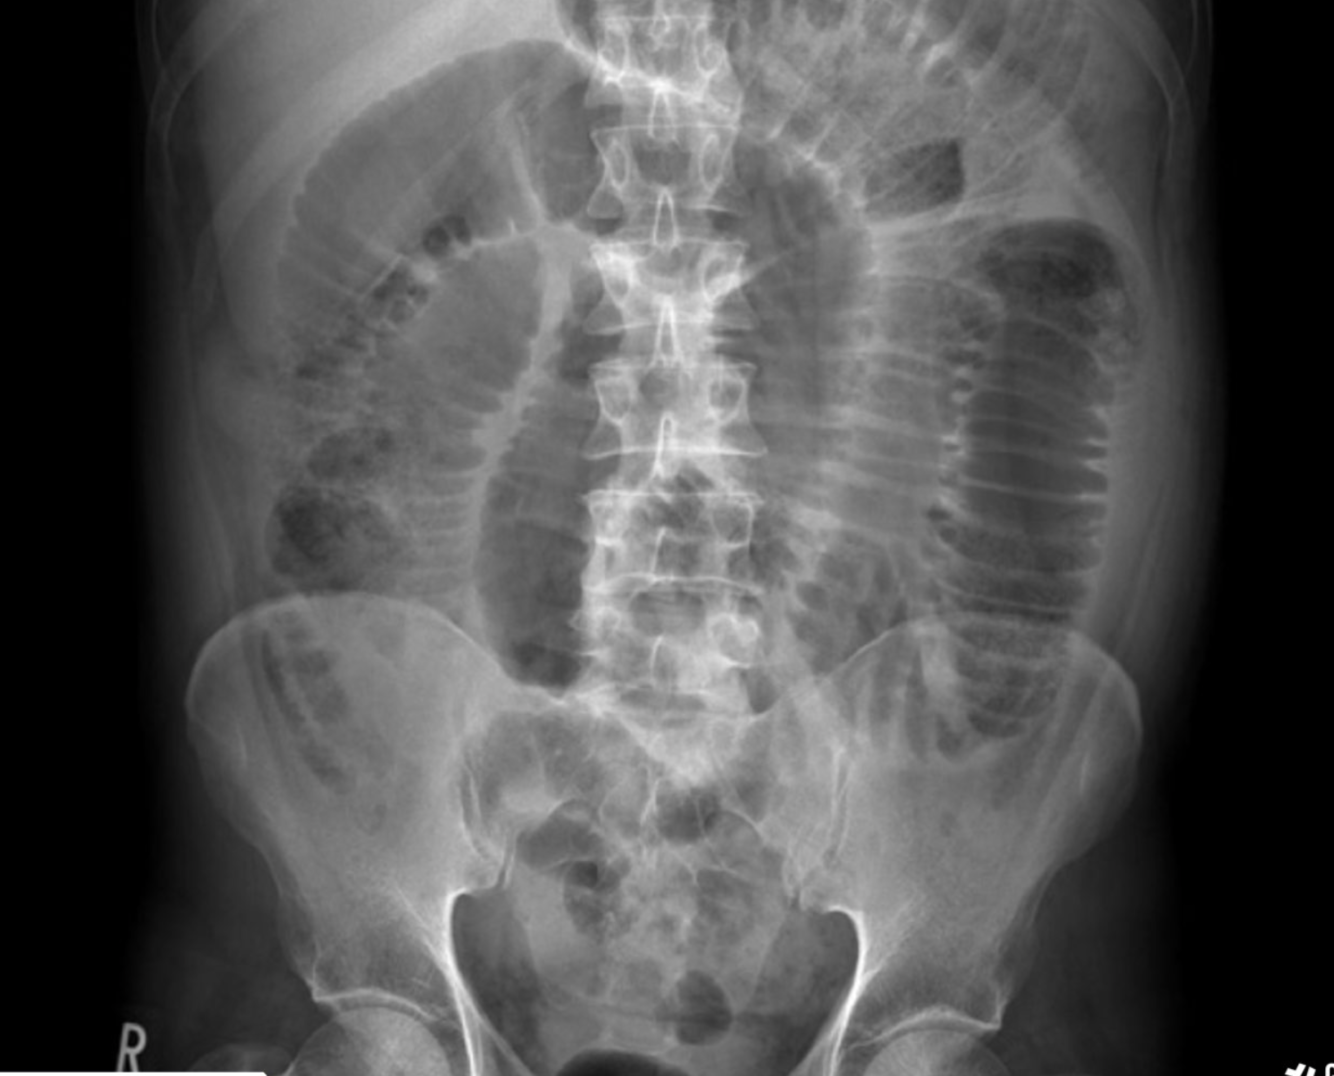

multiple myeloma